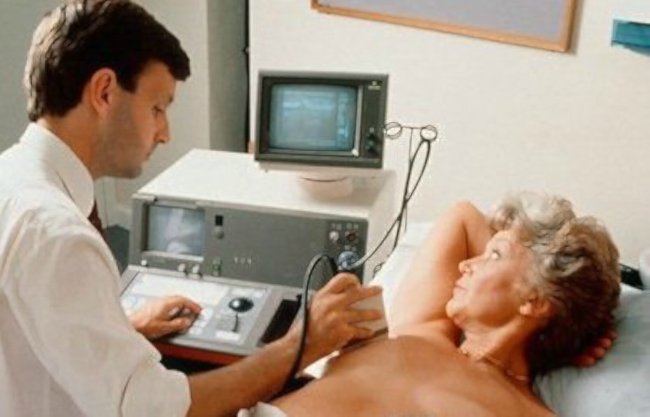

Маммография — это необходимая процедура для любой женщины. Начиная с 40 лет, любая женщина должна ее проходить ежегодно. Именно это исследование выявляет 80-90% всех случаев раковой опухоли молочной железы. Главное, что при таких исследованиях болезнь можно выявить на ранней стадии, а это дает возможность вовремя начать лечение.

98% женщин, у которых раковую опухоль молочной железы диагностировали на ранней стадии, через 5 лет постановки на учет остаются живы и успешно проходят курс лечения. Если же рак достигнет лимфатических узлов, то эта цифра снижается уже до 80%.

Для тех же, кто пропустил симптомы, не проходил диагностику вовремя и в результате выявление рака произошло в стадии, когда он начал поражать соседние органы, выживаемость составляет всего 26%. Кроме маммографии, каждая женщина ежемесячно должна проводить самообследование грудной зоны на предмет появления уплотнений.